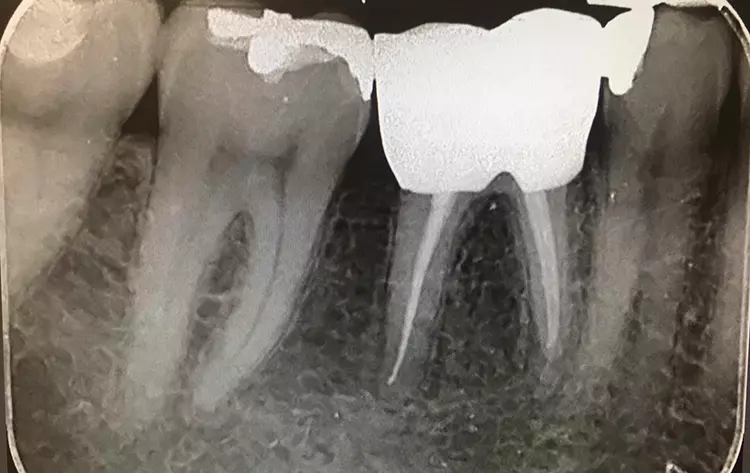

Die klinische Untersuchung zeigte eine klobige Metallkeramikkrone auf Zahn 46. Der Parodontale Screening Index ergab einen Wert von 3 im unteren rechten Sextanten.

Beim Sondieren traten Blutungen auf, die distal von Zahn 46 stärker ausgeprägt waren. Daher wurde an dieser Stelle ein weiteres 6-Punkt-Taschendiagramm erstellt, das Taschen von 4 mm Tiefe auf der distobukkalen Seite von Zahn 46 mit Blutungen zeigte. Zusätzliche Perkussionstests im unteren rechten Quadranten ließen erkennen, dass Zahn 46 nicht auf Perkussion reagierte.